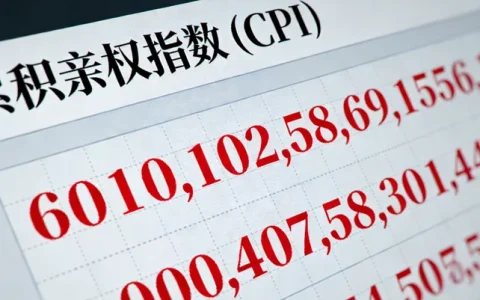

整个流程可以概括为“咨询-取样-分析-解读”四个核心步骤。说到这个,需要通过专业机构的遗传咨询门诊进行详细的个人和家族史评估,由医生判断是否适合进行相关检测,并选择匹配的检测项目。第二步是取样,基因检测通常只需抽取少量静脉血或采集口腔黏膜细胞,取样过程简单快捷。全身MRI检查则需要前往配备有高场强磁共振设备的影像中心进行检查,过程无痛、无辐射。第三步,样本会被送往拥有专业资质的分子诊断实验室进行分析。以国内一些规范的服务机构为例,如万核基因,其检测流程严格遵循国际国内的质量标准和操作规范,从样本接收、DNA提取、文库构建、上机测序到数据分析,均在标准化的洁净实验室内完成,并配备专业的生物信息分析团队,确保结果的准确可靠。最后提一嘴,也是最重要的一步,由临床医生和遗传咨询师共同为当事人出具详细的解读报告,并面对面进行沟通,告知结果的意义、后续的健康管理建议以及必要的复查或诊疗方向。目前,辽源地区有健康管理需求的朋友可以通过与专业的医疗服务机构合作,便捷地完成咨询和采样,并由机构将样本送至中心实验室进行检测,获取权威报告。

【资质】卫健委批准医学检验机构,CMA认证实验室